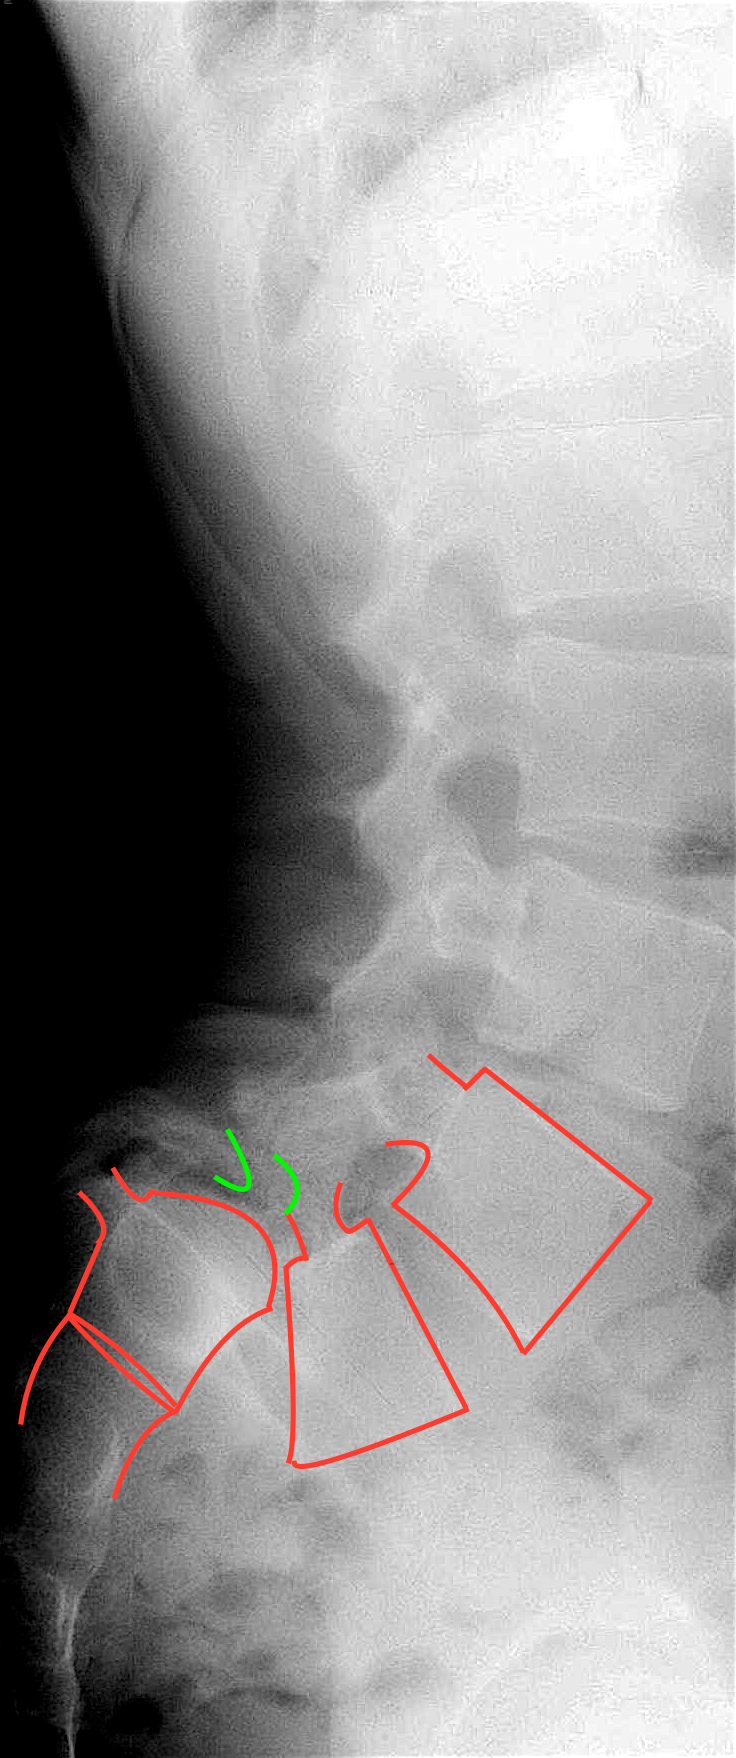

Hochgradiges Wirbelgleiten

Zur Sicherung der Diagnose habe ich ihn ins Spital bestellt. Das Röntgen ergab eine schwere Instabilität und Fehlstellung

zwischen Lendenwirbelsäule und Kreuzbein. Ein sog. echtes Wirbelgleiten 4°.